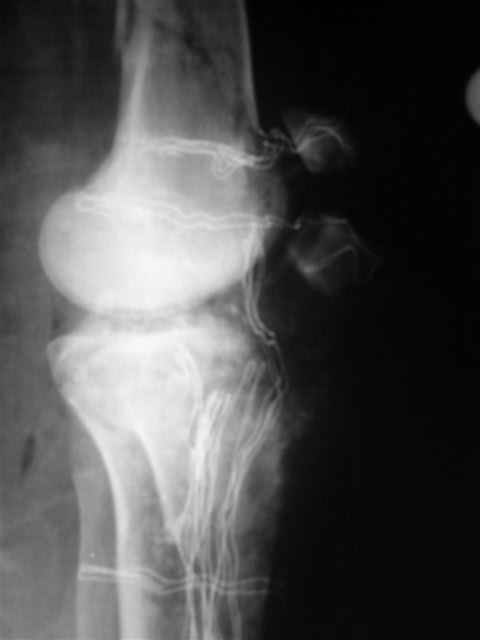

№4 снимок через два дня после операции, супракондилярный перелом, при поступлении конечность была холодная и без пульса, подозрение на повреждение сосудов, сделана ABI (ankle-brachial index) в приемном отделении, индекс меньше 1 к 0.9 в норме 1 к 1.1, срочная ангиография в операционной после Ex-Fix, по два стержня в сегменте наложен в течение 20 мин, повреждение подколенной артерии, ушивание сосудистым хирургом через медиальный доступ в дистальном отделе бедра и двухразрезная профилактическая фацсиотомия, перкутанная фиксация каннюлированными шурупами несмещенного перелома шейки бедра и дополнительные стержни в фиксаторе для жесткости.